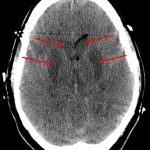

Indication: Post-cardiac arrest

- Diffuse cerebral and cerebellar loss of gray-white differentiation with reversal of gray-white differentiation of the deep gray nuclei

- Global effacement of the ventricular system, basal cisterns, and cerebral sulci with crowding of the foramen magnum

- Severe hypoxic ischemic encephalopathy (HIE)

Diffuse cerebral and cerebellar loss of gray-white differentiation with reversal of gray-white differentiation of the deep gray nuclei. Findings are consistent with severe hypoxic-ischemic encephalopathy (HIE). There is associated diffuse cerebral edema with downward transtentorial and cerebellar tonsillar herniation. No acute hemorrhage or hydrocephalus.